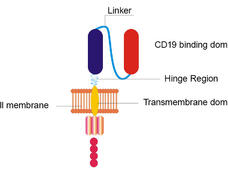

Remodeled CAR T-Cell Therapy Reduces Side Effects in First Clinical Trial

A remodeled CAR T-cell therapy causes fewer neurologic side effects and is equally effective as the original form of the treatment, according to results from the first clinical trial testing the approach in patients with B-cell lymphomas.